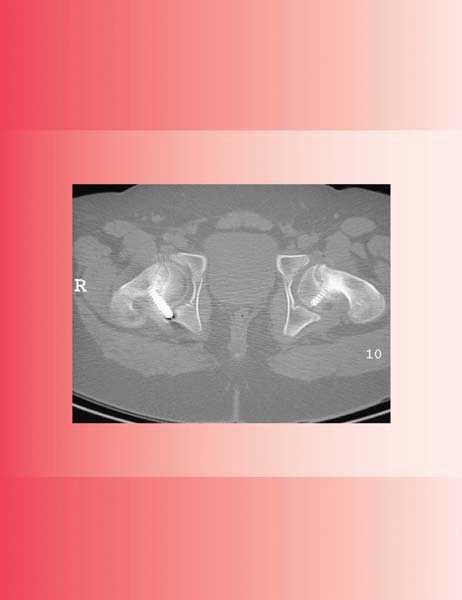

![]()  |

▪ FIGURE 22-4 This 9-year-old girl presented to her primary care doctor with a 4-month history of left hip and knee pain. He obtained knee (A) and hip (B)

films, but relied on the radiologist to detect a problem. Unfortunately for the child and doctor, the radiologist read the films as “normal examination” (C). The child was finally referred to the pediatric orthopaedist two months later. There is now a moderately displaced SCFE bilaterally (D,E).  |